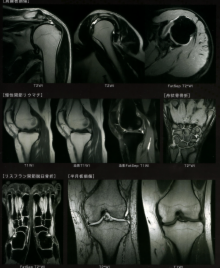

肩・手・足・膝など

CT/MRI画像